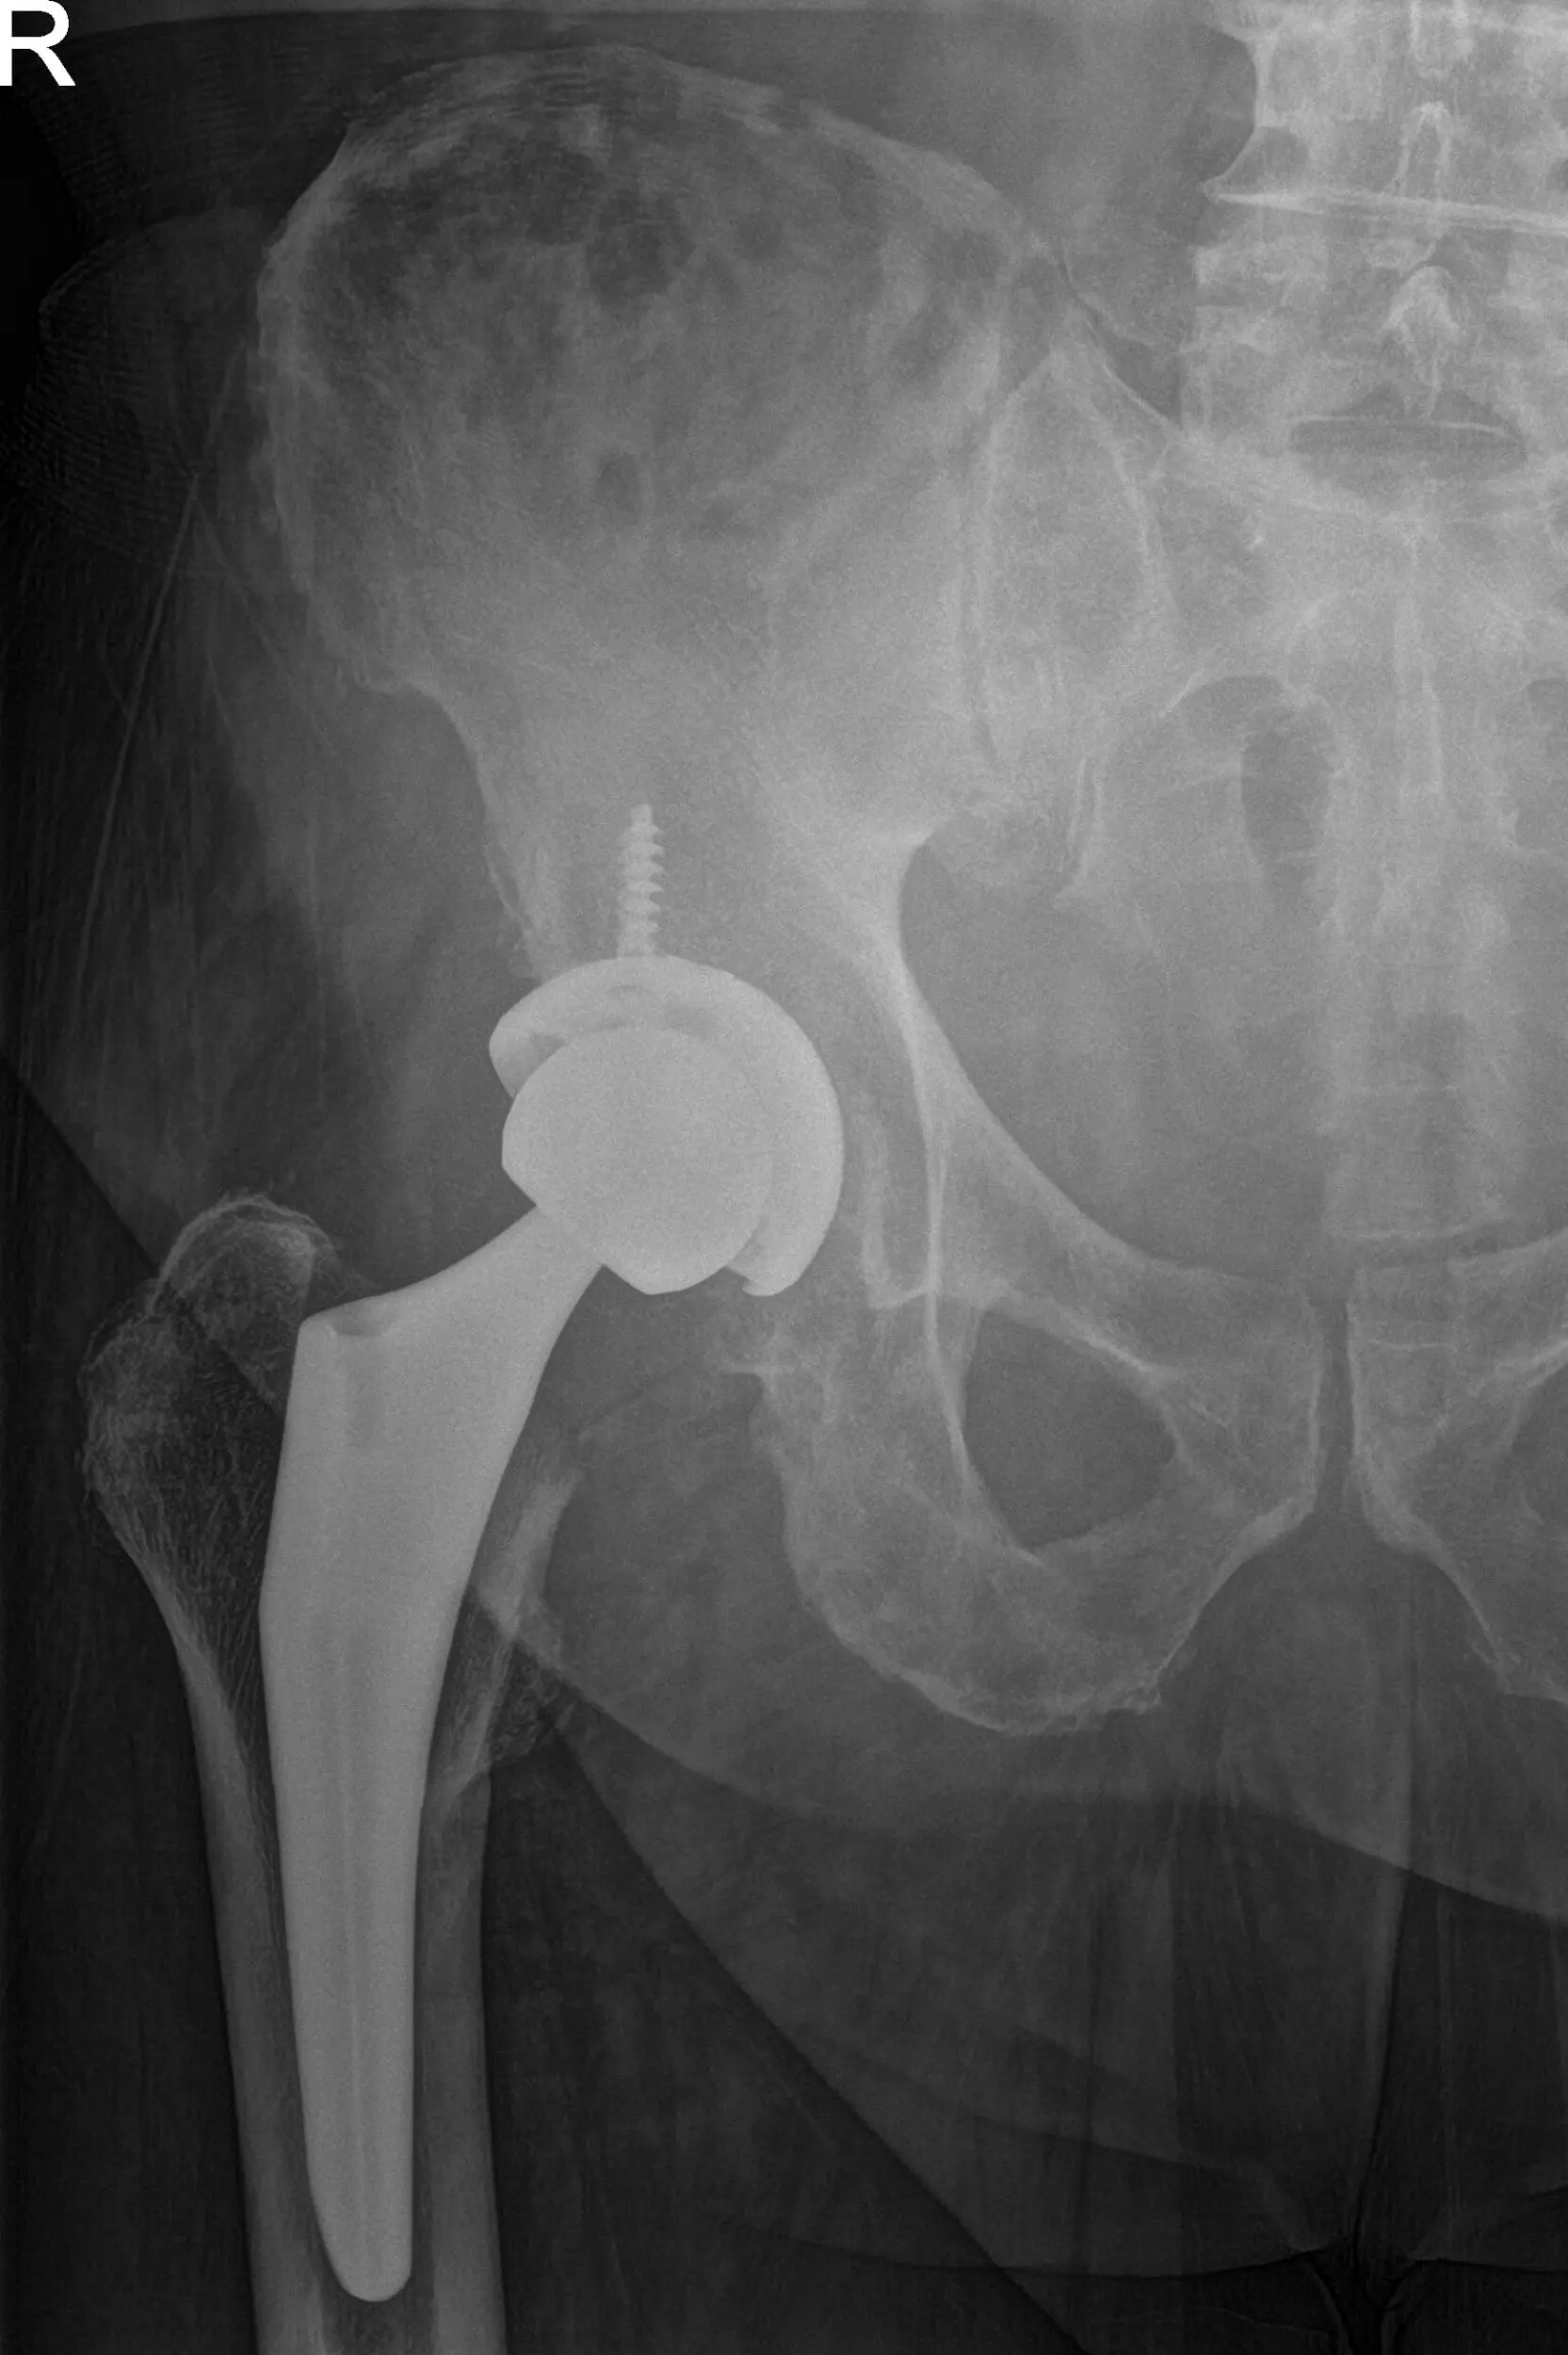

Postoperative X-ray showing AP and frog-leg lateral views of the right hip